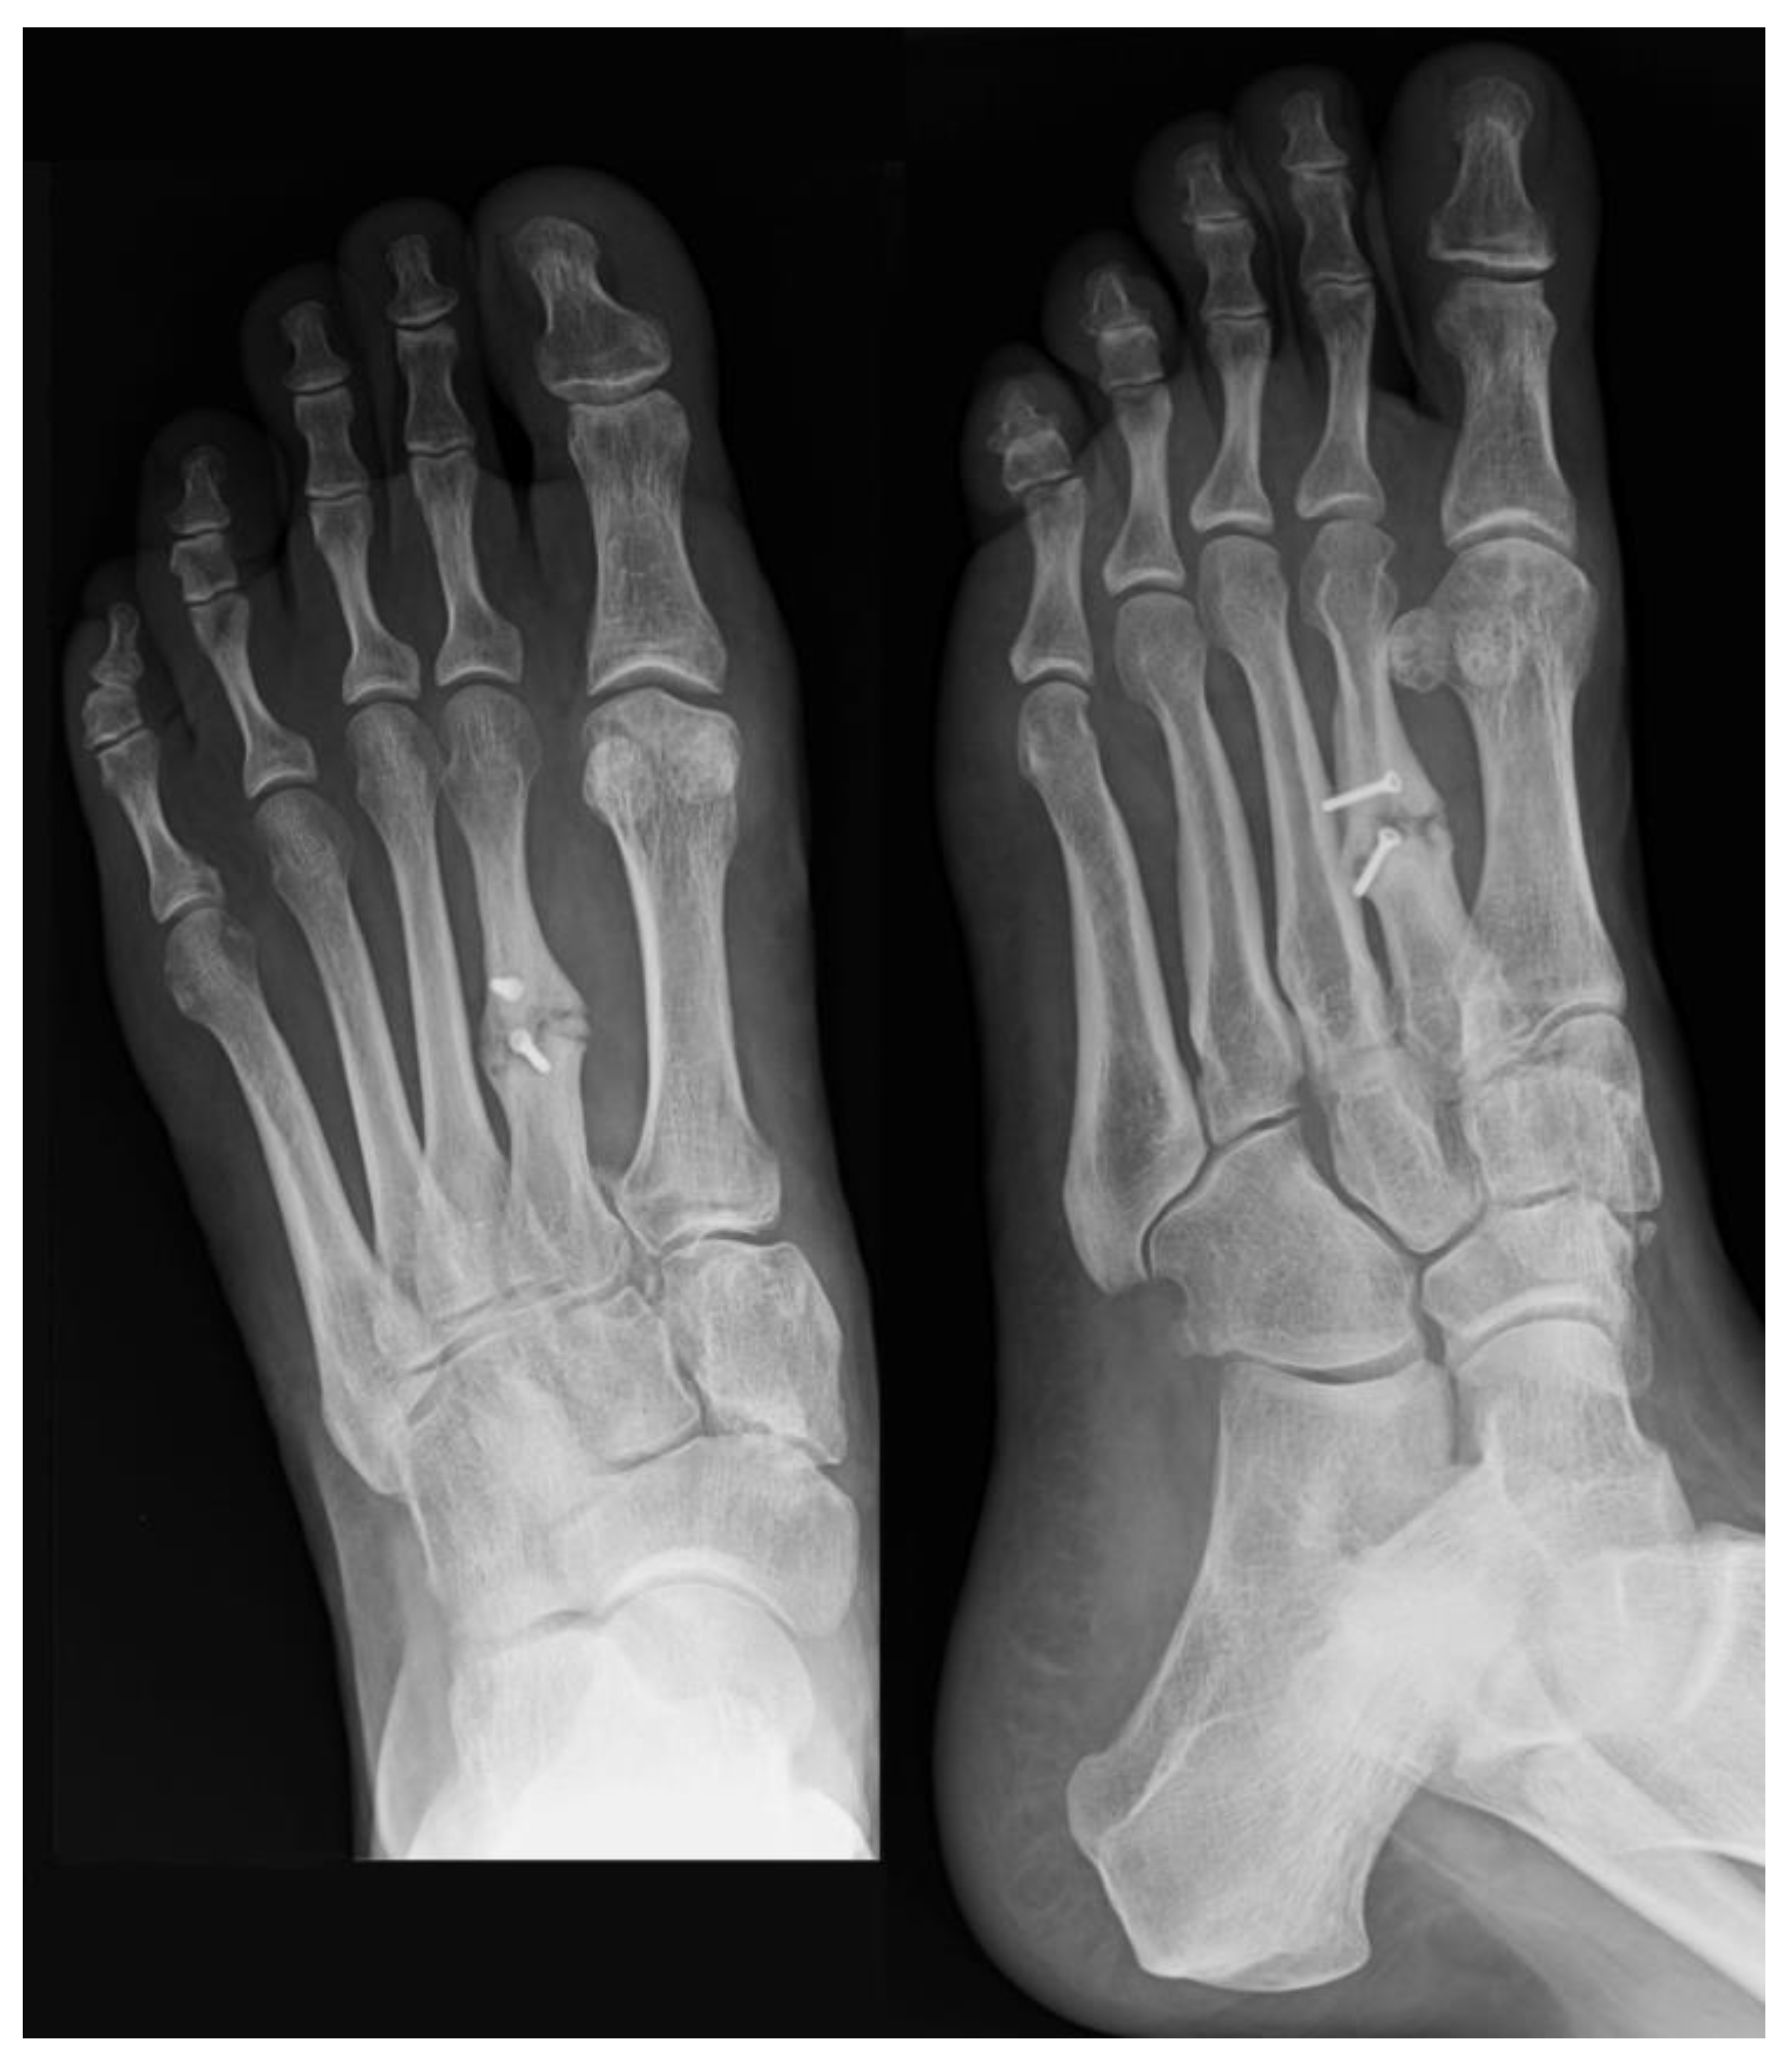

Postoperatively, ambulation was allowed using a heel weight-bearing shoe for 5 weeks. After this period, suture removal and removal of K-wires were performed, followed by progressive weight-bearing with crutches. At 8 months post-surgery, radiographs revealed a solid and well-aligned union and restoration of the correct metatarsal formula (Figure 4), accompanied by a significant clinical improvement. No complications occurred.

Figure 4. Postoperative weight-bearing X-rays at 8 months showing a solid and well-aligned union of the second metatarsal and restoration of the correct metatarsal formula.